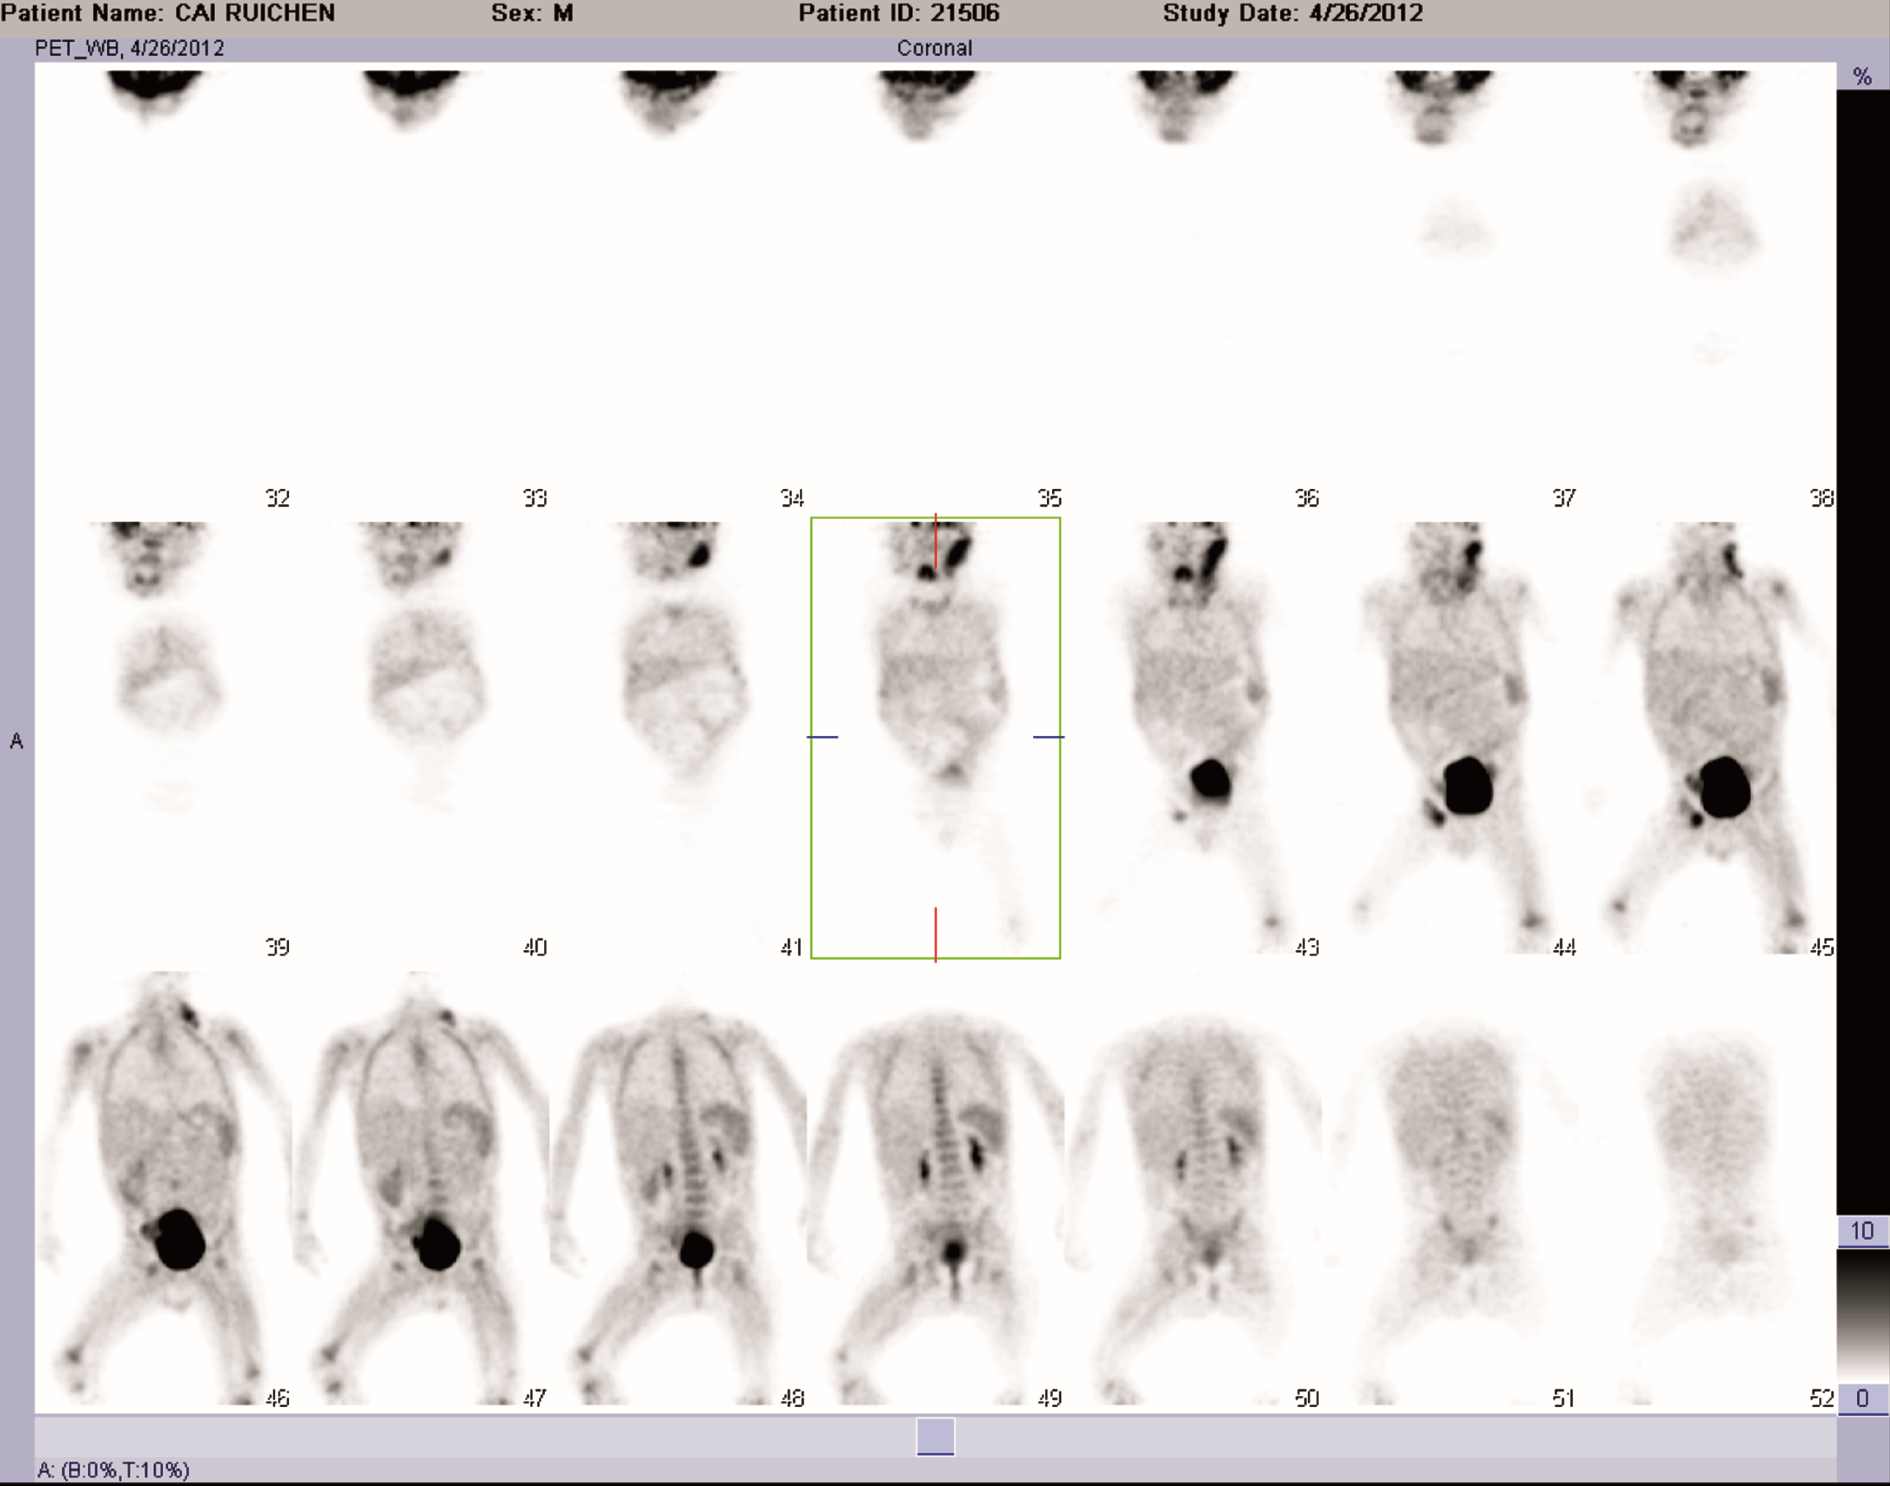

病情变化:采用BFM NHL 2000方案治疗,共6疗程。治疗结束后1个月因“皮疹伴反复发热10余天”再入院。特点:全身较密集红色丘疹伴瘙痒,部分化脓,右耳后、右侧腹股沟0.5~1.0 cm肿大淋巴结,质硬,无压痛,表面光滑。肝肋下3 cm,脾肋下刚触及。体温最高39.4℃,外院予抗菌、抗过敏等治疗,皮疹部分消退,仍发热,白细胞、血小板呈进行性升高,白细胞34.66~55×109/L,血小板646~950×109/L,血红蛋白 114 g/L,血沉:105 mm/h。骨髓涂片:骨髓增生活跃,淋巴瘤细胞占3.0%。PET/CT检查示:①全身多发肿大淋巴结葡萄糖代谢不同程度增高,考虑淋巴瘤影像学改变;②脾肿大、葡萄糖代谢弥漫性稍增高,考虑反应性改变。见 图1 图2。血培养阴性。抗菌治疗无效,2周后出现肛周脱皮,心脏超声提示冠状动脉扩张,诊断川崎病,予静脉注射免疫球蛋白 1 g/(kg·d)×2 d治疗,同时口服阿司匹林及潘生丁维持治疗,体温稳定,皮疹消失出院。

图1 疗程结束1个月后全身PET/CT图像

徐卫平(核医学科副主任医师):PET-CT检查提示全身多发中央及外周长骨骨髓不均匀放射性增高或减低,肝门区可见多发局灶性放射性浓聚,脾脏放射性药物摄取分布弥漫性增高,颈部、锁骨上窝、盆腔、腹股沟区多发淋巴结肿大,以左侧颈部淋巴结尤为显著,而腹股沟淋巴结代谢水平高,纵隔淋巴结肿大,但代谢水平不高。综合上述影像,考虑血液、淋巴系统恶性病变并骨髓、脾脏、肝门区淋巴结广泛浸润可能性大。